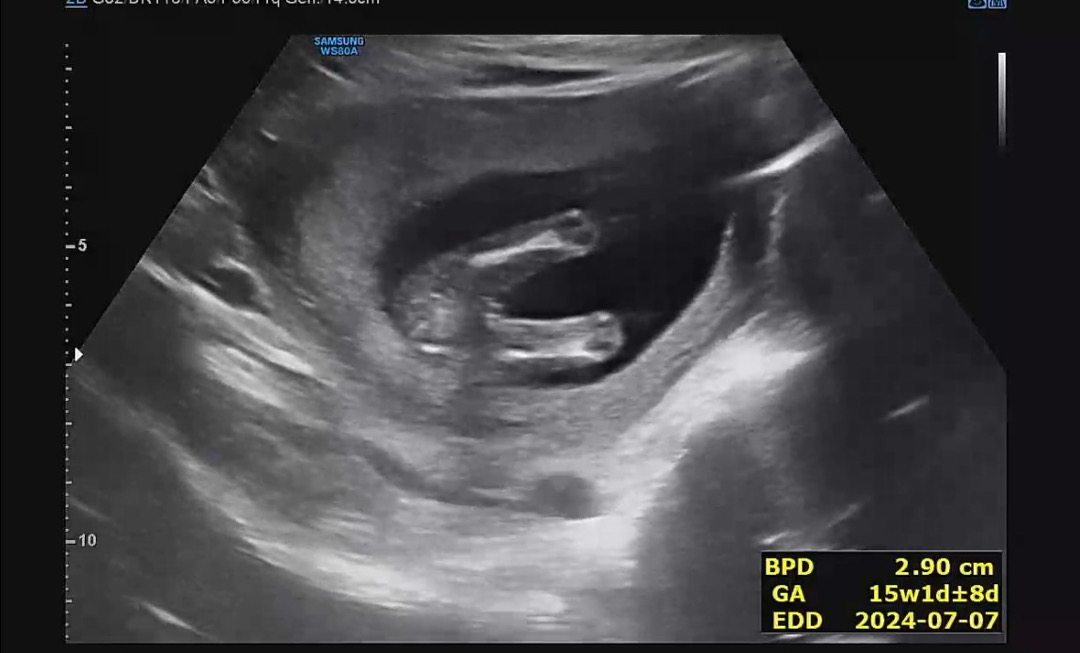

헐 제 초음파인줄 알았어요 ㅋㅋㅋㅋ 너무 똑같은걸요? 딸이라규 하셨어요

다리사이 보면.. 헷갈리는데 딸일까요..?

성별이 너무너무 궁금해서 초음파 보고 왔는데ㅠ ㅜ 애매하다시며...단호박으로 성별 안봐주셨어요.. 딸일지 아들일지 아직..애매한가요ㅠ ㅠ?

첫째 초음파랑 똑같아요 딸이요~

15주면 딸일것같은데용..?!